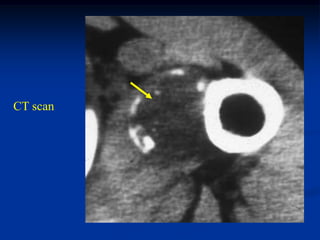

CT scan